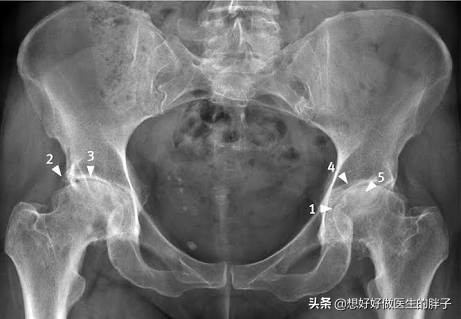

开yun体育app入口登录 髋关节术后康复

恢复后尽快开始。主要目标是提高力量并防止受影响的一侧萎缩。当受影响的肢体完全伸展时,初始训练只允许进行一些等距练习。为了防止髋关节和膝盖屈曲,将枕头放在膝盖下是禁忌。 逐渐调整受影响的肢体最终会导致步行。恢复速度部分取决于完成的手术类型。例如,与互锁的内部指甲和钢板固定或钢针板手术相比,髋关节置换术手术通常会迅速发展而不会过度恢复,并且功...

开yun体育app入口登录 好博Haobro 康复训练器髋关节训练器(重锤式髋关节训练椅) HB-ZC

HeooBro康复训练装置髋关节训练装置(高锤髋关节训练椅)HB-ZC是一种专为髋关节康复训练而设计的设备。该产品具有以下特征: 1。有效的康复:该教练采用重型锤设计,可以提供更大的训练性,并有效增强患者的肌肉力量和髋关节稳定性。通过持续训练,患者可以帮助恢复髋关节功能。 2。安全可靠:该教练由高强度材料制成,具有良好的稳定性和耐用性。同...

开yun体育官网入口登录体育 髋关节疼痛很常见,令很多人苦恼,这些康复锻炼方法您可以尝试下

除了膝关节外,髋关节疼痛可能是最常见的关节疼痛,尤其是那些长时间开车的人,长期从事大量体力劳动并经常进行瑜伽运动的女性朋友以及其他原因,例如喝酒酒精并使用激素。股骨头坏死也是髋关节疼痛的常见原因。因此,由于臀部疼痛的问题,如何进行康复运动?让我们谈谈! 对于髋关节疼痛的朋友,建议不要进行盲目的康复运动,因为并非所有康复运动都适合所有患者...